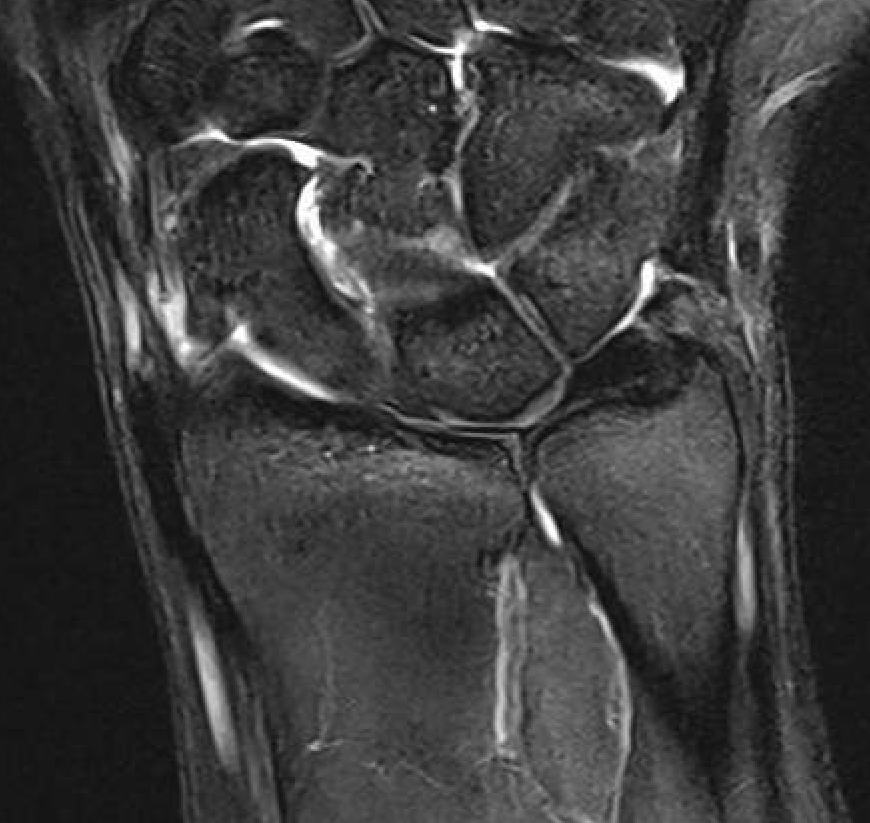

Ulno-carpal abutment

Ulnocarpal abutment and lunate chondromalacia

Ulna positive with ulnocarpal osteoarthritis